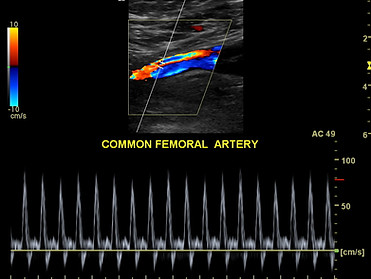

Artery Ultrasound (Extremity)

Arterial Ultrasounds are to evaluate the blood vessel (artery) that carries blood from your aorta to your arms or legs. This test helps rule out plaque, stenosis or narrowing that occurs in the artery itself that might limit blood supply to that limb.

More INFO>>>